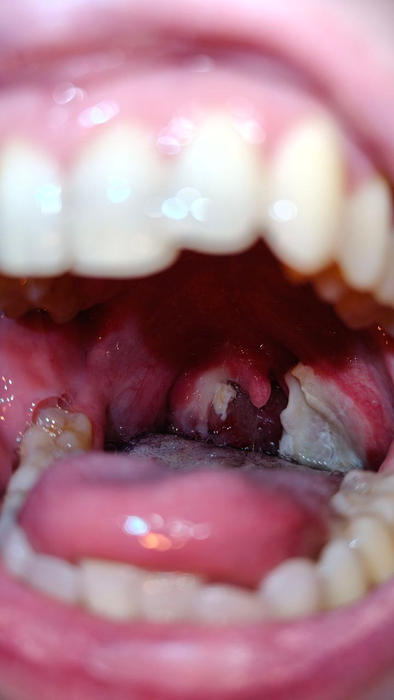

После того как ей вырвали зубы мудрости, жена стала похожа на джокера, потому что у нее остались ранки в уголках губ от расширителя. А через пару недель супруга решилась на криодеструкцию миндалин, чтобы избавится от тонзиллита. Эта операция входит в топ 2 по страданиям, сразу после родов.

В красках не буду описывать какой это пиздец, просто скажу что укол обезбола и нимесил особо не помог. Хотя гугл говорит, что операция в целом безболезненная

•  Meizorika, так я себе удалял все зубы мудрости, тоже норм было. Кроме того, что один врач въебал мне по нижним зубам щипцами, когда выдергивал верхнюю 8ку. А второй когда вырывал нижнюю 8ку так давил на челюсть, что если бы щипцы соскользнули или он бы резко вырвал зуб, то я выглядел бы вот так